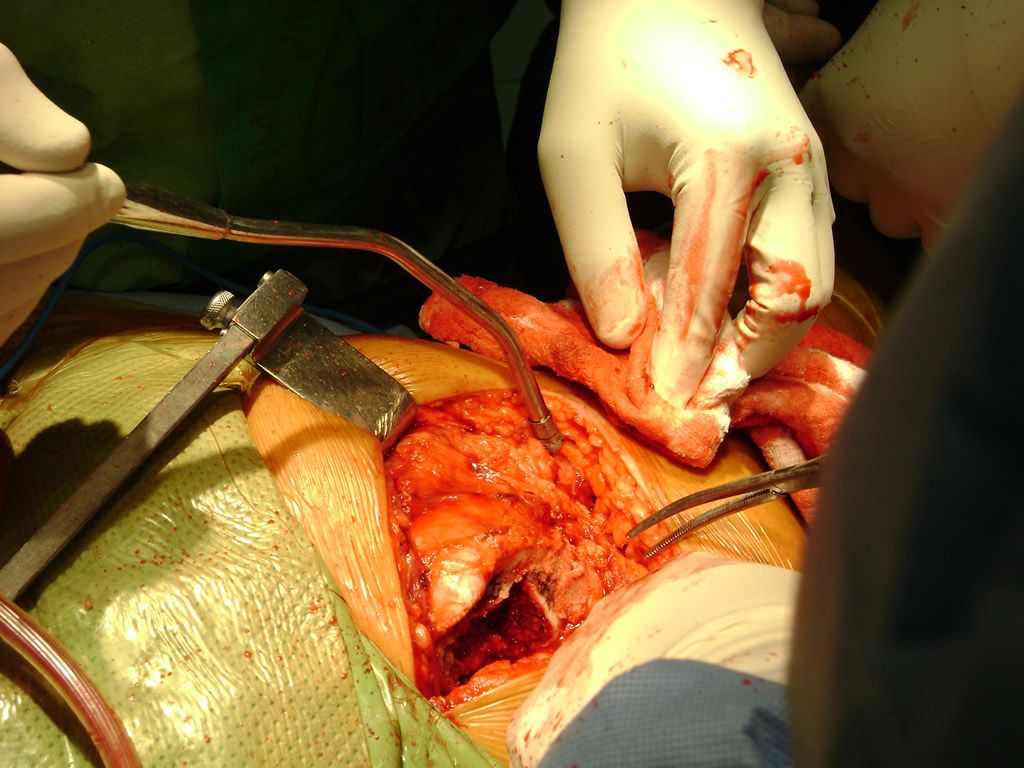

Cirugía de Cadera